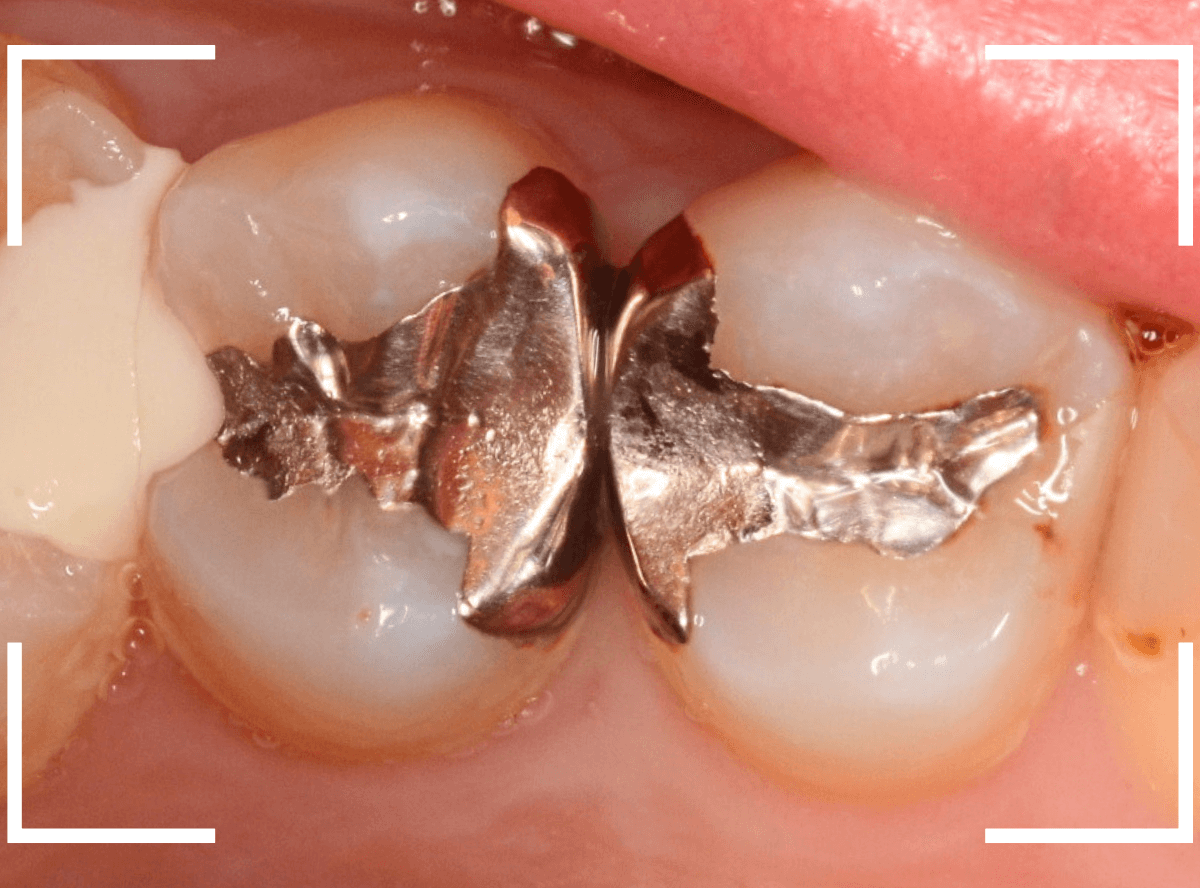

Case.16 金属の周りであちこちから虫歯

検診を希望された患者さんのケースです。

お口の中を拝見すると、上の奥歯の歯のすき間(隣接面)や、変色したレジンの中が怪しい感じです。

レントゲン写真で確認します。

青い線が神経で、赤い線が虫歯と思われる部分です。

奥から3歯が虫歯と思われますが、特に中央の歯の虫歯が深そうです。

まず、中央の歯の金属を除去します。

〇部分は前の治療時にしいたセメントです。この下に虫歯が広がっていると思われます。

セメントを除去したところです。

赤く染め出されているところが虫歯です。

神経に近くなっていますので、診療に虫歯を除去します。

側面のレジンや隣の歯との間の虫歯も慎重に除去します。

かなり広く虫歯が広がっています。

奥の歯の虫歯も全て除去しました。

3歯すべての虫歯を除去したところです。

しばらくお薬をつめて症状を経過観察した後、型どりをしてつめものを再製作する予定です。